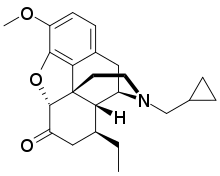

- Semi-synthetic opioids: created from either the natural opiates or morphine esters, such as hydromorphone, hydrocodone, oxycodone, oxymorphone, ethylmorphine and buprenorphine;